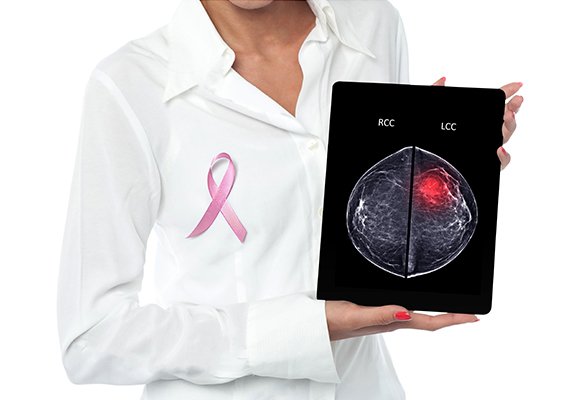

Our surgical treatment for breast cancer delivers excellent results, and is suitable and recommended for clinical or cosmetic objectives:

1) Breast conservation surgeries

2) Sentinel Node Biopsy

3) Breast Reconstruction Surgery

4) Advanced Cosmetic Surgery

5) Oncoplastic Surgeries

6) Scarless Surgeries

Systemic Therapy for Breast Cancer Treamtment

We offer multiple medical modalities for the breast cancer treatment, including chemotherapy and targeted therapy. All these modalities are suggested to a patient according to the particular stage and biopsy of cancer.